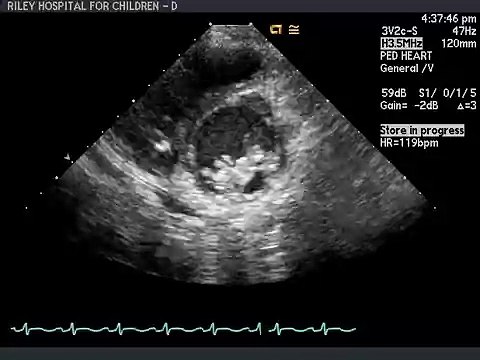

TTE 27

Uploaded: June 18, 2016 Views: 1